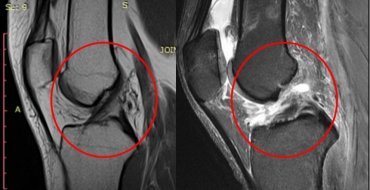

МРТ в діагностиці пошкоджень хрестоподібних зв'язок